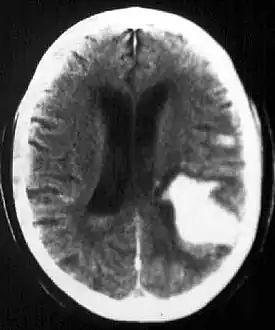

| Multiple intraparenchymal hemorrhage | |

Intraparenchymal hemorrhage (IPH) is one form of intracerebral bleeding in which there is bleeding within brain parenchyma. The other form is intraventricular hemorrhage (IVH).[1]